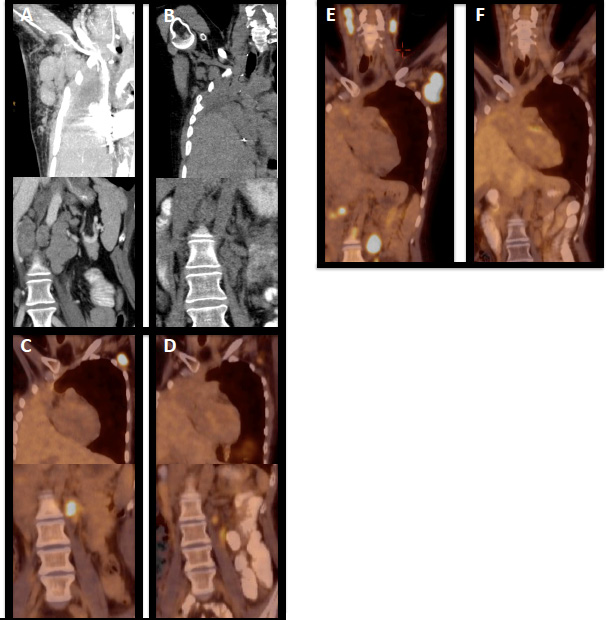

When she presented to us, the patient suffered from severe B symptoms, showed massive nodes, had a highly inflammatory lab and underwent a combination of pixantrone, paclitaxel and G-CSF. She developed sepsis with opportunistic infection from which she slowly and only partially recovered. In February 2015, then 83 months after the primary diagnosis, the patient was severely ill with tachycardia, dyspnea, multiple small nodular pulmonary infiltrations, a 5 cm pericardial infiltration, large mediastinal, hilar and subdiaphragmatic nodes as well as new liver lesions (stage IVEB) (Figure 1A). Her LDH was 492 U/l (normal range 135-225 U/L), CRP 23.7 mg/dl (normal range < 0.6 mg/dl), the temperature was 37° C without definite signs of infections, her blood pressure had dropped to 87/58 mmHg, and her heart beat rate was 126/min.

Figure 1: Course of disease under immunologic treatment. (A) CT scan showing massively enlarged axillary and subdiaphragmal lymph nodes prior to the start of nivolumab, (B) CT control two months after start of nivolumab showing massive regression of nodes in both regions, (C) 18FDG PET/CT in progression during nivolumab and prior to start of ipilimumab (D) treatment response during ipilimumab (E) 18FDG PET/CT cervical, axillary , and subdiaphragmal lymph node progression after ipilimumab and prior to start of ruxolitinib (F) 18FDG PET showing ruxolitinib-induced remission.

Nivolumab at a dose of 3 mg/kg was started and the patient improved immediately even during infusion (vanishing of pruritus, cardiovascular improvement). She achieved a PR as documented by CT scan as of May 2015 (Figure 1B) and was kept on the drug with excellent tolerability and without relevant side effects. In October 2015 she developed pruritus and the control 18FDG PET/CT scan in November 2015 showed relapse in cervical, retrolaryngeal, subpectoral and axillary nodes (Figure 1C). Due to the previous pneumonectomy radiotherapy was withheld, nivolumab was stopped and the patient was switched to ipilimumab at a dose of 3 mg/kg beginning in November 2015. The patient again achieved a clinical response and a PR in 18FDG PET/CT scan (Figure 1D). However, in March 2016 elevations of liver enzymes, i.e. glutamat-oxalacetat-transaminase (NCCT grade 4), alanin-aminotransferase (NCCT grade 4), gamma glutamyltransferase (NCCT grade 3), alkaline phosphatase (NCCT grade 3), and bilirubin (NCCT grade 2) were observed although the liver synthesis capacity remained unchanged. The 18FDG PET/CT in April 2016 showed a mixed response with a significant remission in axillary lymph nodes on the left side, but with some new neoplastic lesions in the right axilla. Ipilimumab was stopped due to hepatotoxicity and steroids implemented. Her liver values recovered slowly and completely, but unfortunately she further progressed from Hodgkin lymphoma with rapidly growing and symptomatic nodes in June 2016 (Figure 1E), which was histologically confirmed. She was switched to ruxolitinib at a starting dose of 20mg daily (10 mg bid) and then 50 mg daily (25 mg bid)) and again within days showed decrease in node size, pruritus and B symptoms and she entered remission in 18FDG PET/CT scan in September 2016 (Figure 1F). She relapsed in November 2016 underwent radiotherapy of skeletal disease and due to enlarged lymph nodes in February 2017 was switched to lenalidomide 20 mg q21d and cyclophosphamide 50 mg/po q28d and again showed immediate shrinkage of lymph nodes. As of October 2017 the patient is very well without any B symptoms and without restrictions in her daily life. Treatment is associated with a complete vanishing of palpable nodes, which recur when treatment has to be stopped for reasons of drug-induced cytopenia, but nodes rapidly disappear within days when treatment is started again.